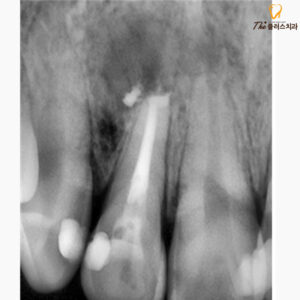

엑스레이를 확인해 보니

염증이 있는 부위는 엑스레이 상에서

검은색의 투과상으로 보이며,

이전에 신경치료를 받으셨던

치아 뿌리 끝 부위로

염증이 생겨 있었습니다.